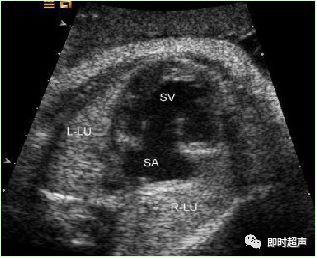

三、胎儿脑室轻度扩张(MVM)

胎儿脑室扩张是最常见的脑发育异常之一,发生率约0.03% ~ 0.15%,脑室扩张时,侧脑室后角最先受累侧脑室后角宽度作为常规衡量侧脑室宽度一个指标。

侧脑室轻度扩张 评价脑室系统体部脉络丛水平 侧脑室壁内缘测量

各种原因造成脑脊液循环受阻,积聚于脑室内,出现脑室扩张。侧脑室宽度≥15mm的明显脑室扩张称为脑积水。多为中脑导水管狭窄所致,原因包括染色体异常、炎症、肿块压迫等。

超声检查脑室扩张的临床意义:

平均宽度为6. 4 ± 1.2mm,正常上限值为10mm;

脑室宽度 10 ~ 15mm 为轻度脑室扩张;

一侧或双侧脑室扩张 > 15mm,为重度脑室扩张,即脑积水,往往预后不良。

超声轻度胎儿脑室扩张的处理:

✔ 轻度脑室扩张合并颅内外结构畸形或脑发育异常的可能性大大提高,因此建议在 18 ~28 周进行系统超声检查。

✔ 超声检查发现单纯性轻度脑室扩张,应定期随访,每隔 2 ~4 周复查 ,了解脑室扩张的宫内转归,因约 14%的脑室扩张为进展型,且预后不良。

单纯性轻度脑室扩张 <12mm,孕期进行超声定期随访,如无进展者预后良好; 如脑室扩张12 ~ 15mm,或有进展者,应建议行胎儿头颅 MRI 检查,必要时行胎儿羊水或脐血染色体核型分析,出生后严密随访神经行为的发育。